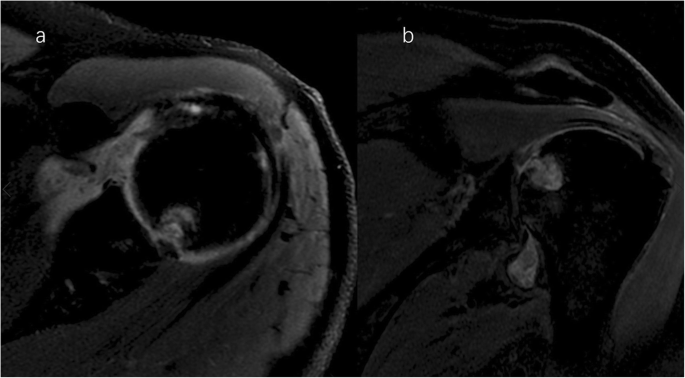

A clinical evaluation revealed that his right shoulder joint had a limited active range of motion, and the passive range of motion was nearly normal. On palpation, tenderness was noted in the anterior and posterior aspects of the shoulder joint, and there was no warmth, erythema, swelling, or redness. When the patient’s upper limb was raised, abducted, and externally rotated, the shoulder joint had a sense of movement, and there were a popping sound and a feeling of shoulder reduction. Gouty tophi were observed on the dorsal aspect of the bilateral great toe and extensor aspect of the bilateral elbows; all of the patient’s other joints were clinically normal, and the examination revealed nothing else of note. Plain radiographs of the affected shoulder showed glenohumeral joint space narrowing, erosions of the glenoid, and osteophyte formation on the inferior aspect of the glenoid. At the superolateral point of the humeral head, a lytic lesion (arrow) was detected, and malunion of the right clavicle fracture was also seen (Fig. 1). To assess the integrity of the soft tissue of the shoulder joint, we ordered a magnetic resonance imaging (MRI) examination, which revealed that the axial and coronal proton density-weighted, fat-suppressed MRI exhibited an intact rotator cuff, joint effusion, synovial proliferation, effusion within the biceps long head tendon sheath, humoral head superolateral cystic erosion, posterior humeral head subluxation, and severe glenoid erosion (Fig. 2). A laboratory examination revealed an elevated uric acid level of 594 µmol/L (normal range 208.00-428.00 µmol/L), erythrocyte sedimentation rate (ESR) of 65 mm/h, C-reactive protein level of 34 mg/L, leukocyte count of 8.35 × 109/L, and hemoglobin level of 12.8 g/dL. The patient had a negative test for rheumatoid factor and anti-citrullinated protein antibodies (ACPAs). The liver and kidney function of the patient were normal. No abnormalities were found on electromyography of the upper extremities. In consideration of the possibility of shoulder joint infection or malignancy, arthrocentesis was performed, and 20 ml of fluid was aspirated. The fluid was macroscopically cloudy and yellow. The synovial analysis revealed an inflammatory cell count with leukocytes 5200/mm3, which were predominantly neutrophils. Gram staining of the fluid was negative, and no organisms were cultured. A cytology analysis and the joint fluid Xpert MTB/RIF test were negative. A polarizing microscope was not available in our hospital; therefore, we could not examine the synovial fluid for crystals.

Right shoulder magnetic resonance imaging (proton density-weighted fat-suppressed sequence ). Axial (a) and coronal (b) views revealed intact rotator cuff, joint effusion, synovial proliferation, effusion within the biceps long head tendon sheath, humoral head superolateral cystic erosion, posterior humeral head subluxation, and severe glenoid erosion